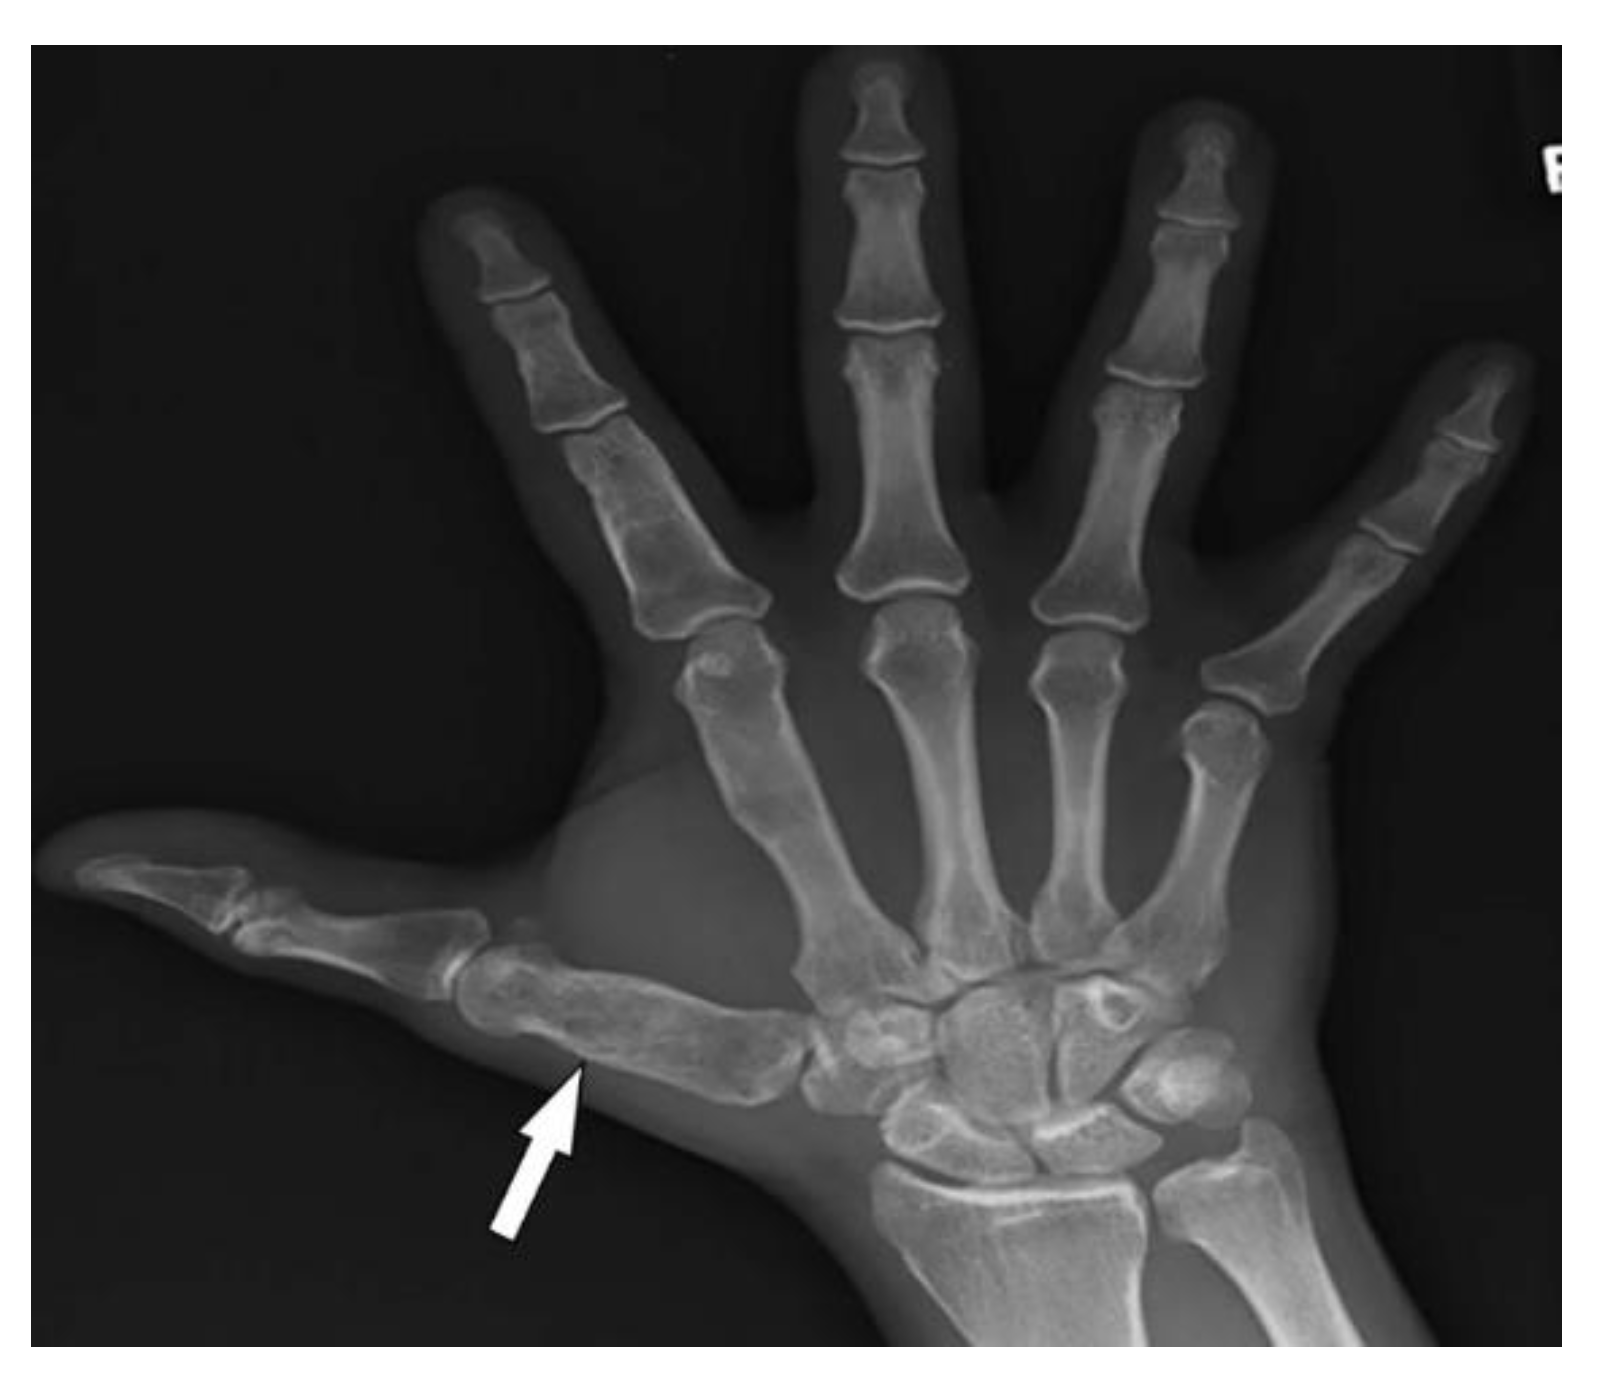

3.9. Fong Disease

| Fong (Nail–patella) syndrome | Hypoplastic nails, triangular lunulae Hypoplastic patellae Focal segmental glomerulosclerosisLester iris | Bilateral absence of patellae Posterior iliac horns (Fong’s prongs) Subluxation of radial heads |